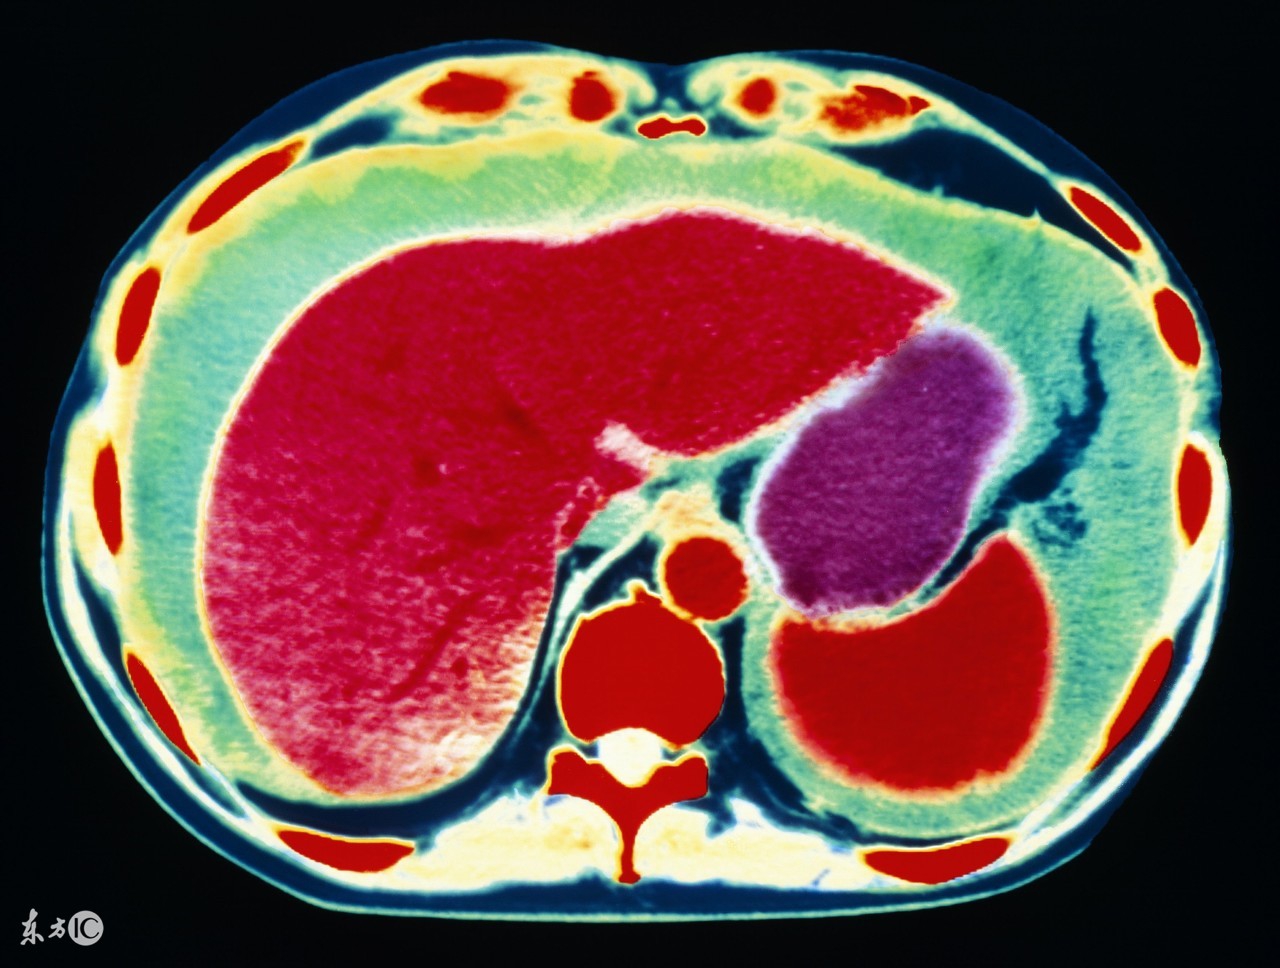

很多人都听说过腹水,也就是大家说的肚子里积了很多水,最熟悉的应该是肝腹水,所谓肝腹水,就是指肝病引起的腹水,除了肝病相关的腹水,癌症是引起腹水最主要的原因。有哪些癌症会引起腹水?

1、肝癌。前面说了,肝病是引起腹水最常见的原因,其中肝癌就是其一。原发性肝癌,发展到一定程度,合并腹水的可能性非常大,其实本质上仍是肝硬化所致,所以肝腹水就是肝硬化腹水。肝硬化时,肝细胞变性、坏死、纤维组织增生,肝内血管床受压、扭曲、变形、狭窄,阻塞了血管,使肝窦淤血,血流量大大降低,门静脉压力升高,同时,毛细血管静脉压力也升高,久而久之,胃肠道、肠系膜、腹膜等血液回流受阻,血管通透性升高,血液中的血浆成分外漏,形成了腹水。肝功能不合,肝脏不能合成白蛋白,低蛋白血症,由于血清白蛋白的降低,血管内胶体渗透压下降,血浆成分外渗而形成腹水。所以,不管什么肝病,到了肝硬化,肝功能不全的阶段,就可能形成腹水。

3、卵巢癌,包括输卵管癌、原发性腹膜癌,这三种癌症的治疗原则是一样的,这类癌症也是引起腹水的最常见原因之一,女性如果有大量的腹水,要首先排除卵巢癌可能,有针对性的重点查一查卵巢输卵管。

总结一句话,引起腹水的癌症最常见的是三种癌症:原发性肝癌、胃癌、卵巢癌。其他癌症也可能合并腹水,便相对少见些,所以如果出现大量腹水,而且考虑癌症的话,首先要考虑肝癌、胃癌和卵巢癌,然后考虑其他癌症。但不管什么癌症,都意味着晚期,预后不好,不过,卵巢癌有些例外,即便有腹水,有时也可考虑减瘤性手术,通过手术和化疗等治疗,有相当比例的病人生存时间可达一年以上,不少病人可达两三年甚至更长。